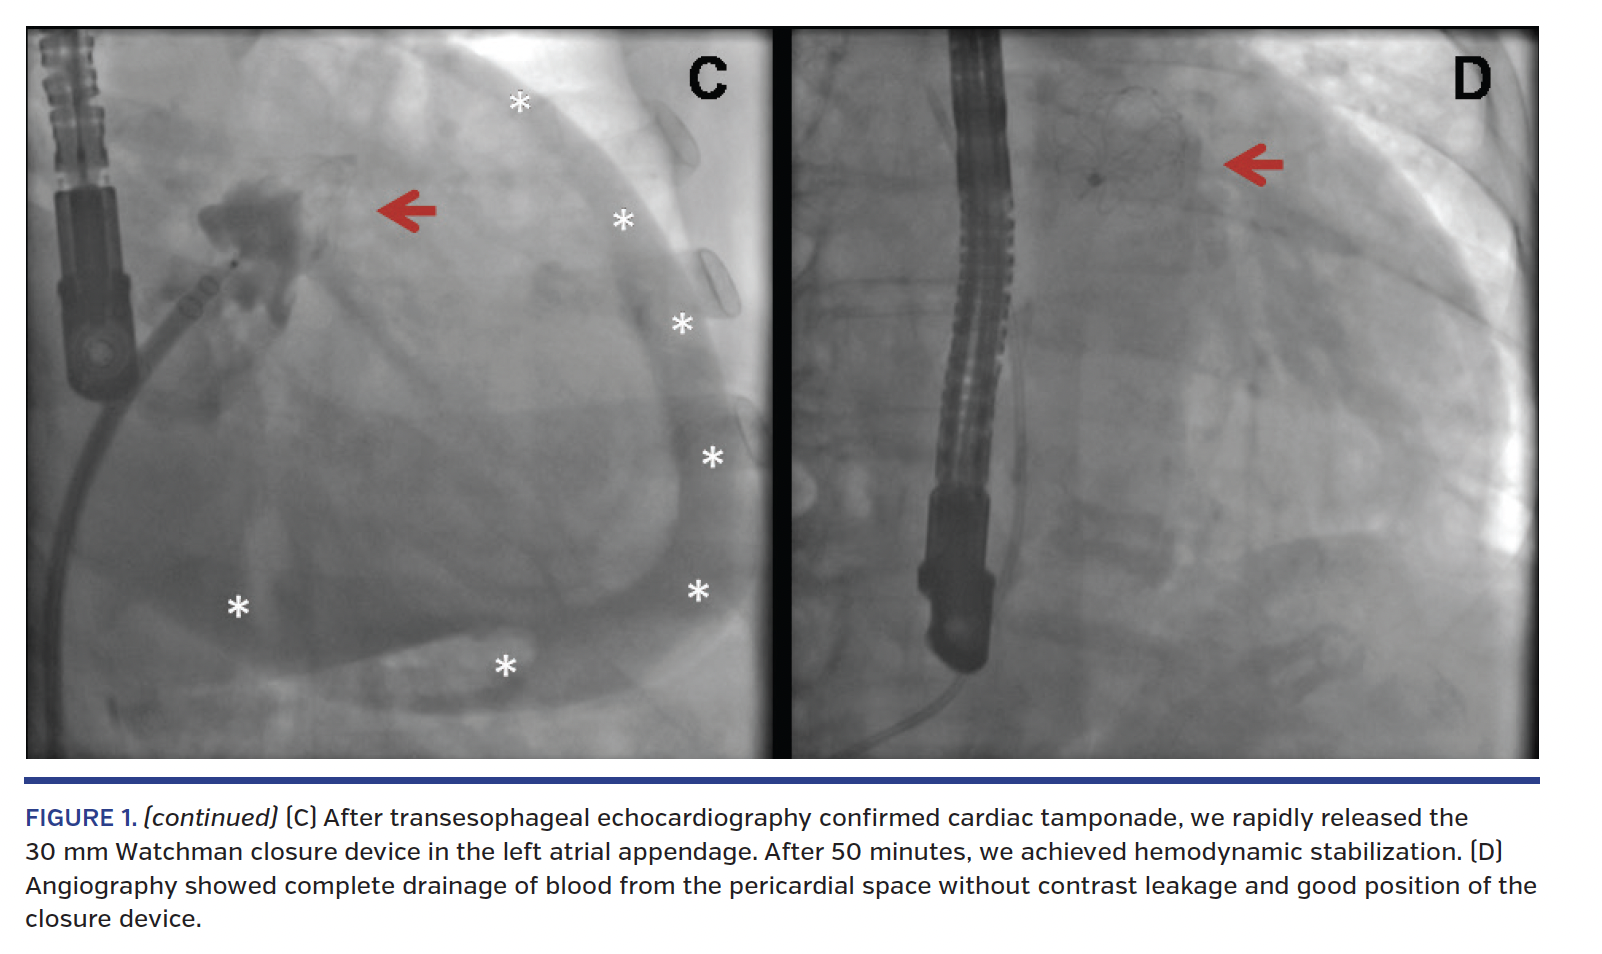

We proceeded as follows: (1) rapid release of 30 mm Watchman closure device in the LAA (Figure 1C); (2) pericardial drainage and aspiration of 1100 mL of blood; (3) autotransfusion with direct reinfusion of 950 mL of blood through right venous femoral access; and (4) infusion of 50 mg intravenous protamine sulfate.

After 50 minutes, we achieved hemodynamic stabilization; angiography (Figure 1D) and TEE showed complete drainage of blood from the pericardial space without contrast leakage and good position of the closure device. The patient was transferred awake to the intensive care unit to continue monitoring.